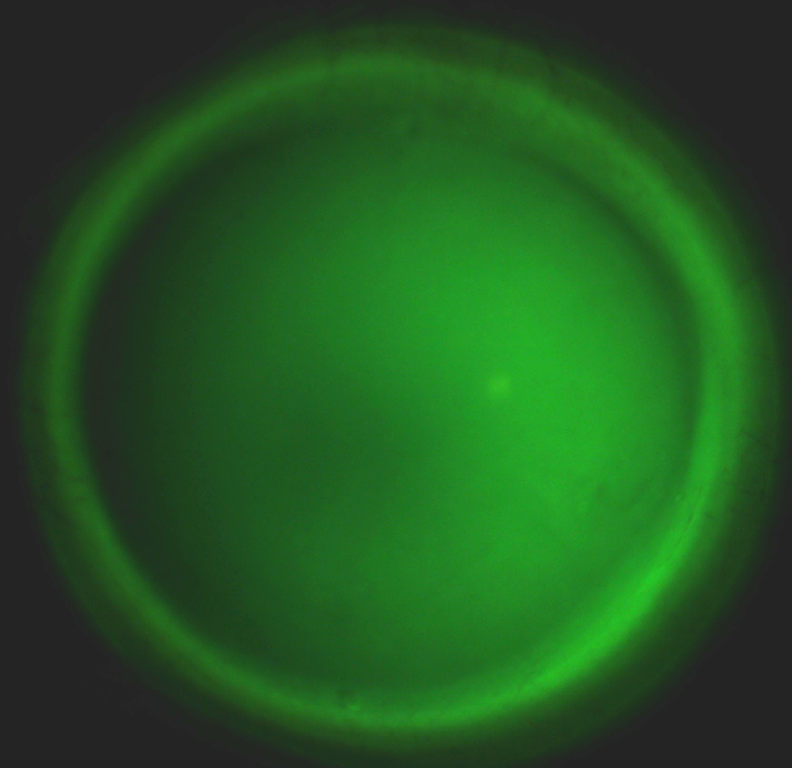

Il nostro protocollo applicativo , sviluppato nel corso di molti anni di attività professionale prevede l'utilizzo tecnologie innovative come la tomografia a coerenza ottica e la profilometria sclero corneale per offrire ai nostri utenti il massimo in termini progettazione e controllo delle lenti a contatto fornite .